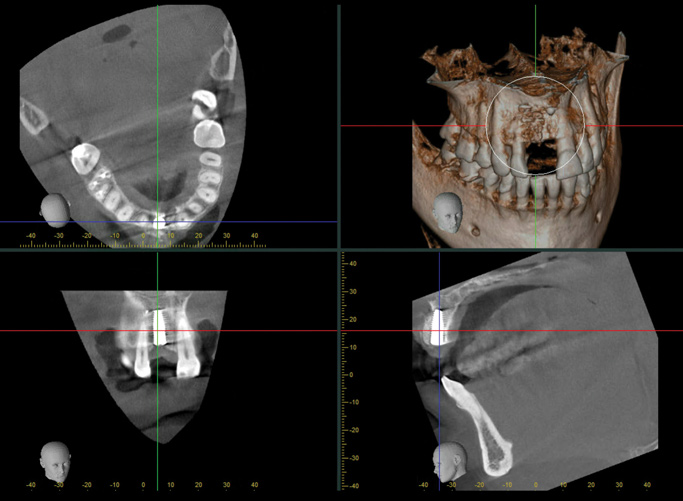

A 56-year-old female patient was referred for the evaluation of tooth No. 8 (Figure 4 and Figure 5). A periapical radiograph indicated that the tooth had undergone apicoectomy and received an excessively long post (Figure 6), and a cone-beam computed tomography (CBCT) scan of the site revealed a lack of buccal plate bone (Figure 7).

When the patient returned 4 months after the initial procedure for reevaluation, she underwent supportive periodontal therapy and was provided with detailed oral hygiene instructions (Figure 13). An intraoral scan and a postoperative CBCT scan were taken to evaluate both the horizontal and vertical hard- and soft-tissue gain. Next, implant planning software was used to merge the STL and DICOM data, which facilitated the creation of a digital wax-up (Figure 14).

The digital wax up allowed the implant position to be planned based on the ideal prosthetic position of the final restoration (Figure 14). The planned implant position adhered to the aforementioned guidelines for ideal implant placement regarding the buccal, interproximal, and apical bone, and its platform would be located 4-mm apical to the planned restorative margin. In the coronal plane, the implant was centered with the gingival zenith in a position that was located approximately 1-mm distal to the midline of the edentulous space. Following implant planning, a tooth-supported surgical guide was designed and then 3D-printed to facilitate fully guided surgical implant placement.

(7.) Pretreatment CBCT scan.

Figure 7

(14.) Three-dimensional implant treatment planning.

Figure 14